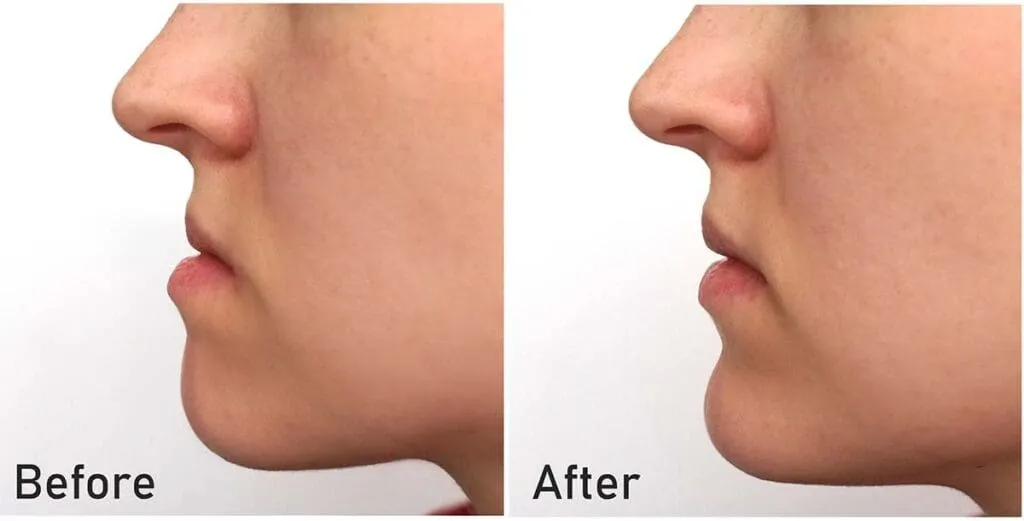

Improved Bite Function

Proper alignment fixes overbites, underbites, and crossbites, making chewing and speaking easier.

Proper alignment fixes overbites, underbites, and crossbites, making chewing and speaking easier.